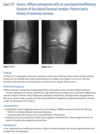

A sagittal proton-density MR image of the

right knee (Fig. 2.15.1) shows a normal posterior cruci-

ate ligament (PCL, arrow) with an apparent second PCL

underneath (i.e., “double-PCL” sign; arrowhead). A sag-

ittal proton-density image through the edge of the

medial meniscus shows increased signal intensity in the posterior horn of the medial meniscus. diminished visualization of the anterior horn,

and lack of the characteristic bow-tie appearance of the meniscus at this site. A corresponding coronal proton-

density image reveals the displaced meniscal fragment

in the intercondylar notch.

Displaced bucket-handle tear of the

medial meniscus

Bucket handle tear is a longitudinal meniscal tear with central, unstable fragment migrates into

the intercondylar notch.

As seen arthroscopically,

the migrated fragment represents the handle of the

bucket, and the portion of the meniscus remaining

in situ represents the bucket

On 4-mm sagittal images, the medial menis-

cus should have a bow-tie appearance on at least

three consecutive MR slices. If the meniscus is not

seen on all these slices, then the coronal images

must be scrutinized to confirm that the meniscus

is intact.

double-PCL sign is produced by displace-

ment of the meniscal handle fragment into the in-

tercondylar notch, where it comes to rest anterior

and inferior to the PCL.

“flipped meniscus” sign. This

sign consists of a shortened posterior horn with

an abnormally tall anterior horn (>6 mm) on sag-

ittal images.

Figure 2.15.5, in which there is a

full-thickness ACL tear causing a double-PCL sign

(arrowheads) and a bucket-handle tear of the menis-

cus that is flipped anteriorly, causing an abnormally

tall meniscal anterior horn (arrow).